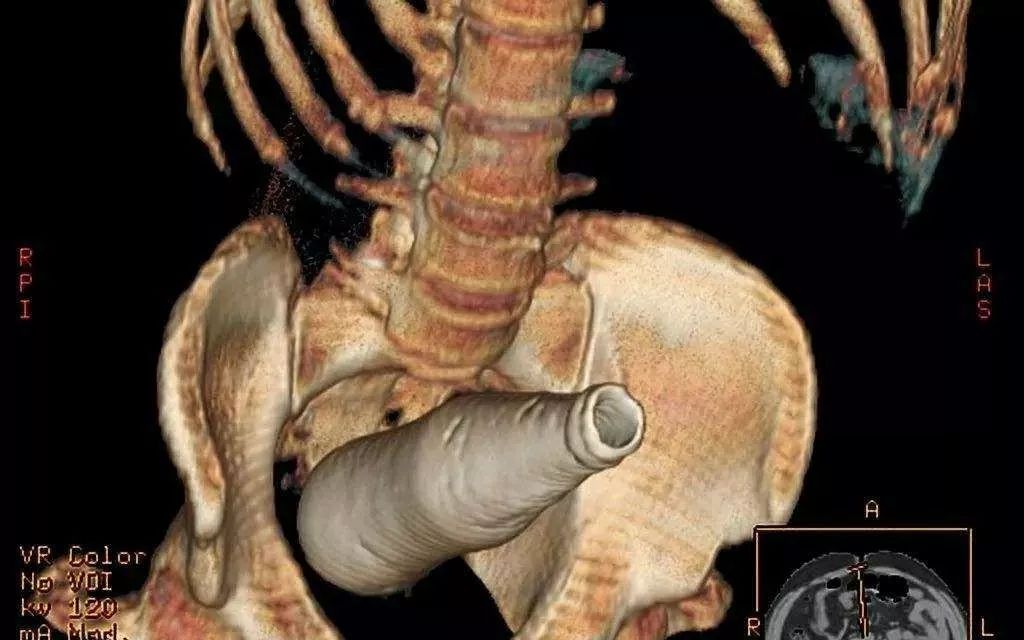

那些年被强塞进体内的异物大盘点